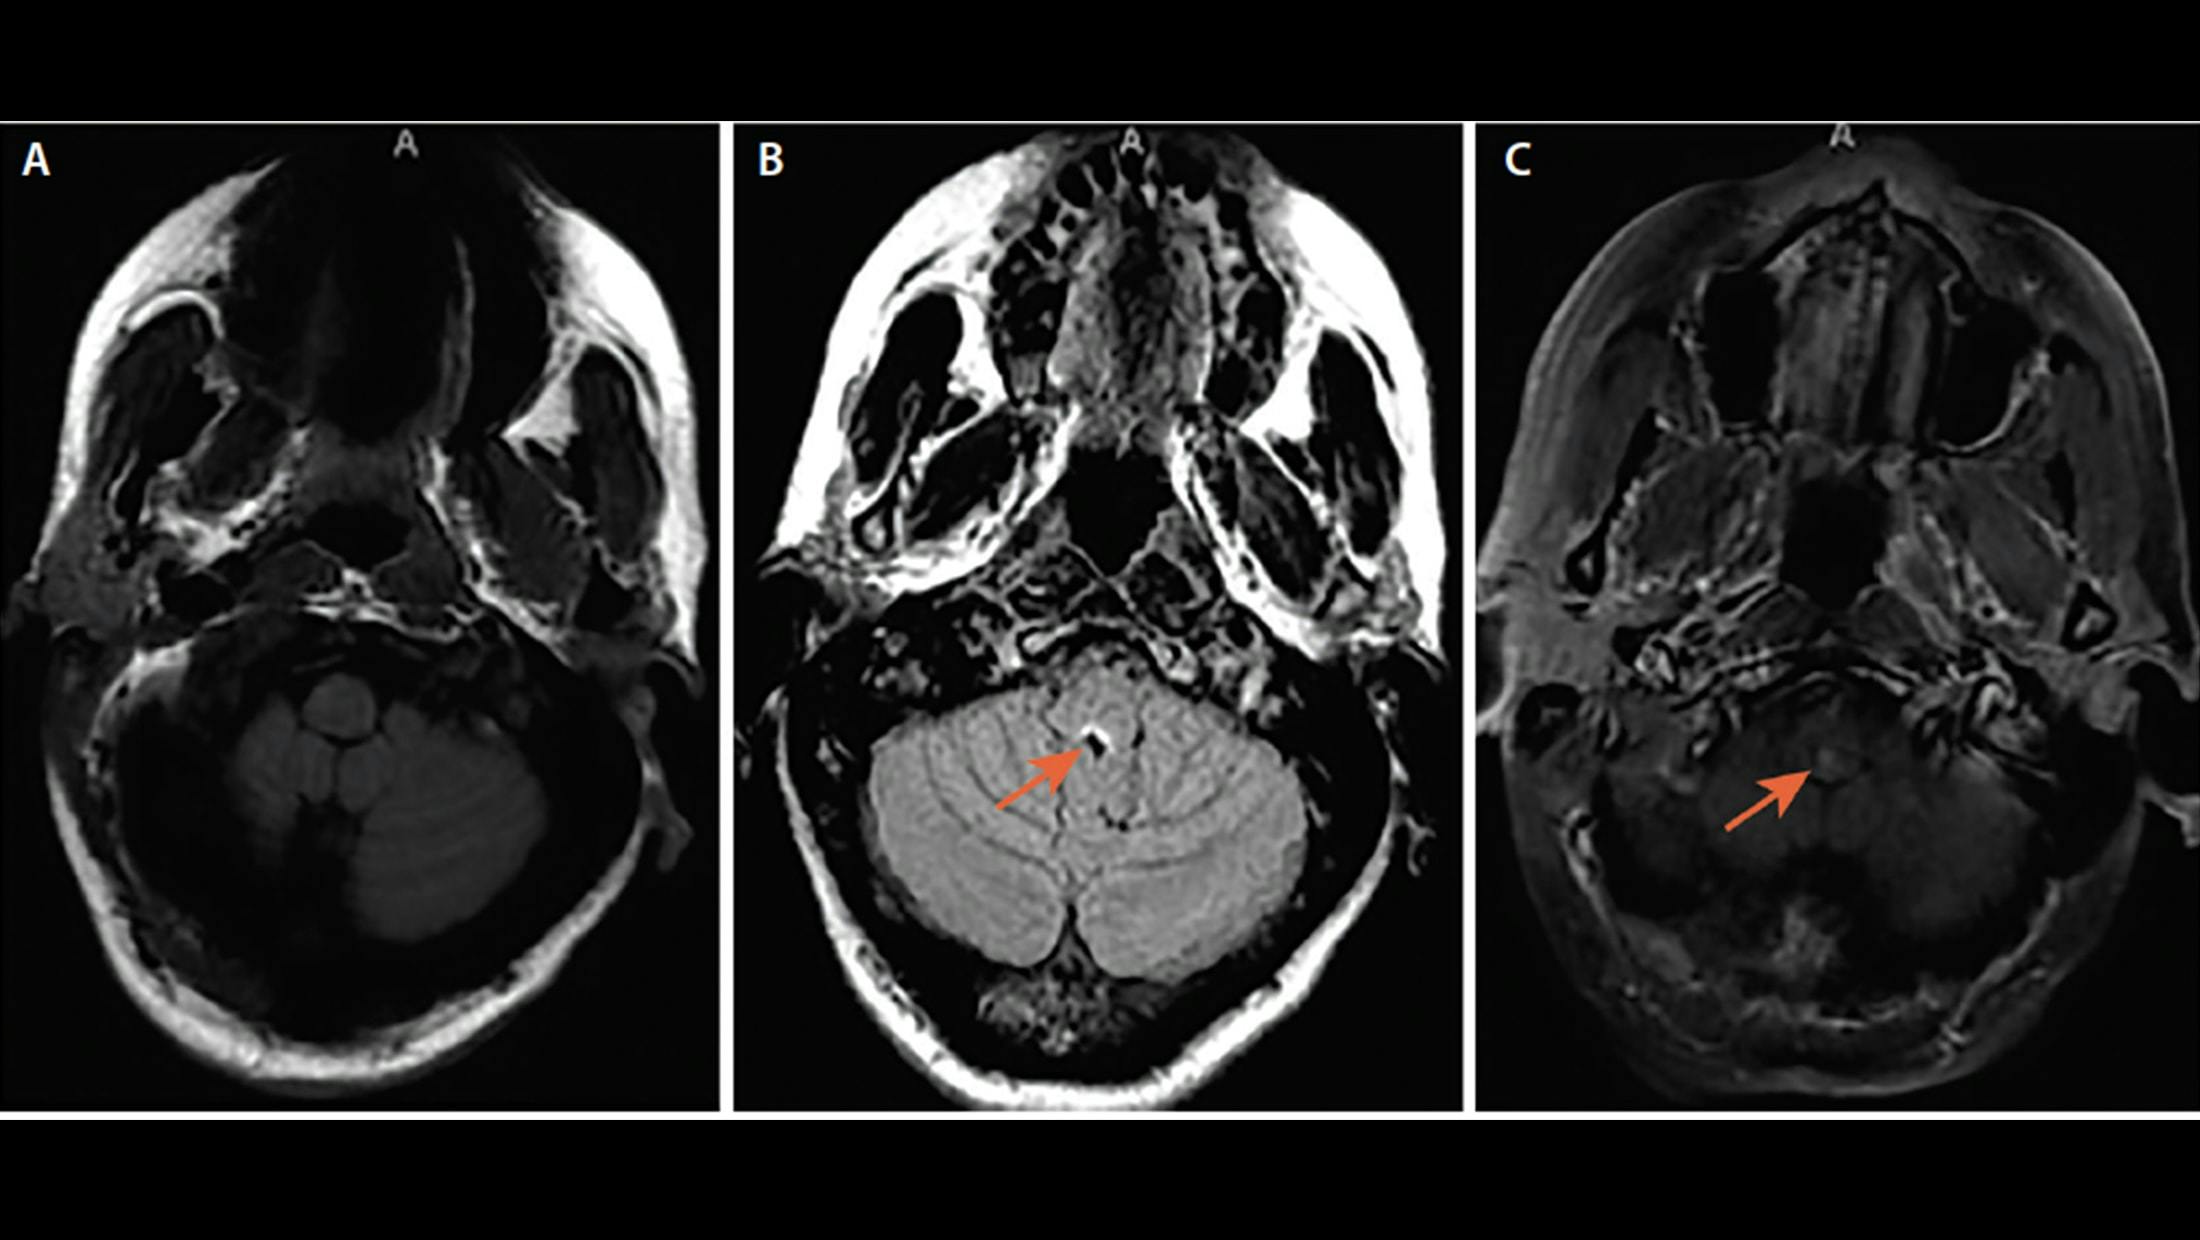

A. Area Postrema Syndrome From Dorsal Medullary Lesion. Axial brain MRI (A) show T2 hyperintense lesion in the dorsal medulla.

B. Area Postrema Syndrome From Dorsal Medullary Lesion. Axial fluid-attenuated inversion recovery (FLAIR) MRI show T2 hyperintense lesion in the dorsal medulla.

C. Area Postrema Syndrome From Dorsal Medullary Lesion. Axial T1-post gadolinium MRI shows enhancement of the dorsal medullary lesion.